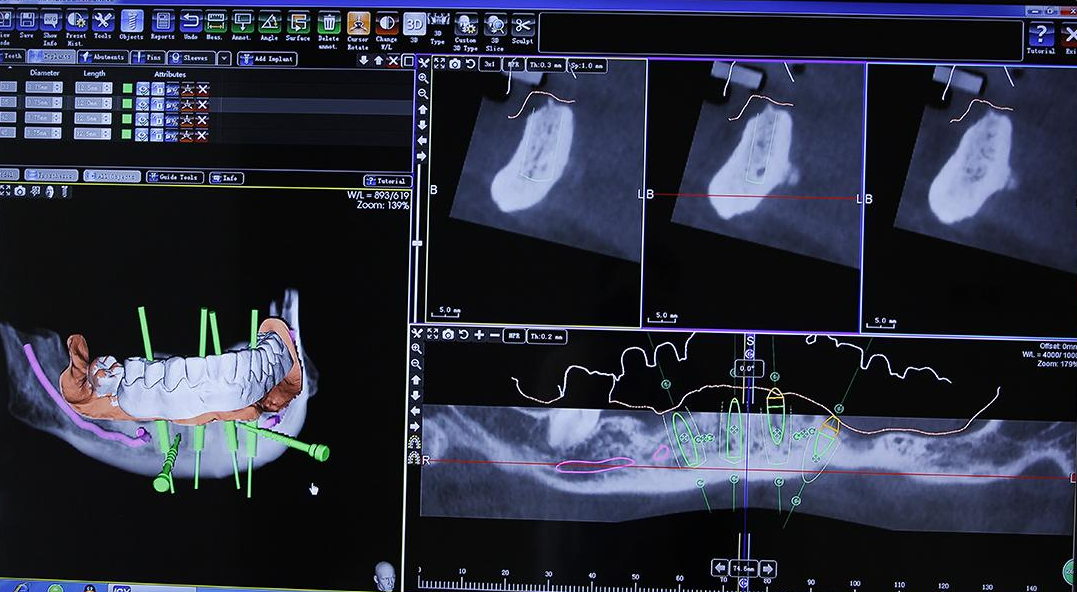

种植牙齿之前,口腔检查必是不可少的步骤,查看口腔的具体情况,牙槽骨密度、邻牙的牙周组织、牙体组织及根尖等情况。

然后,医生会询问顾客病史,如是否有高血压、糖尿病等。充分评估顾客的口腔条件,为患者全面排除隐患后,才能进行种植。

然后医生会根据各人情况,设计种植方案,如确定种植系统、种植体的数量、位置、方向、长度,制作出种植手术需用的3D导板等。

正式开始种植牙手术。把设计好的3D导板套在患者口腔内,在3D导板的““导航”下钻一个孔,把种植体“埋”进去,一般种一颗需要10分钟。将牙骨床内严密缝合,大约一个星期后可以拆线。